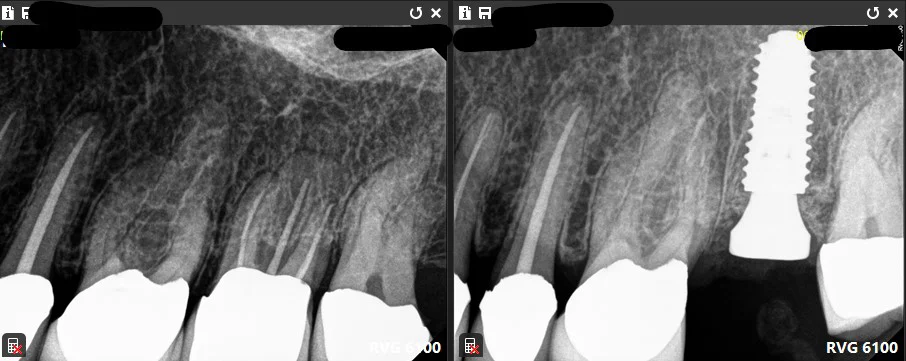

(In this case, the molar has root fracture. It was extracted and an implant placed at the same day.)